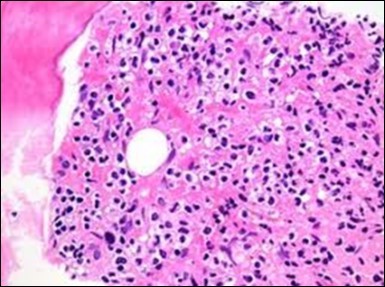

Figure 1.HCL: hairy cells infiltrating designated spaces(17).

The leukaemia cells may enunciate a characteristic immune phenotype, crucial for a confirmatory diagnosis. The peripheral blood mononuclear B cell population may display a kappa or lambda light chain restriction. The phenotype of classic hairy cell leukaemia may be delineated by concurrent, immune reactive CD19+ CD20+,CD 11c+, CD25+, CD103+ and CD123+. An intensely immune reactive CD200+ and a non reactive CD27- antigen may be present2, 4. Evaluation of a trephine bone marrow biopsy and bone marrow aspirate may define the degree of tumour infiltration. A dry tap on account of prominent bone marrow fibrosis may be elucidated at preliminary diagnosis. A decline in the normal haematopoiesis may account for a hypo-cellular marrow in 10% instances. Gradation of cellular infiltrating of the leukaemia within the bone marrow may be appropriately investigated with immune –histochemical stains2, 4. Immune staining for CD20+, annexin 1 and VE1 (a BRAF V600E stain] may validate the diagnosis and precisely analyse the extent of malignant bone marrow infiltration[8]. Determination of BRAF V600E mutation may be critical in therapeutically non responsive individuals with applicable standard therapy or in instances of multitudinous reoccurrences[9]. Deploying inhibitors of BRAF V600E gene may be efficacious in patients impervious to approved therapy. The mutation necessitates a comprehensive scrutiny of the implicated individuals with a sensitive molecular assay which may discern up to < 10% of the hairy leukaemia cells appearing in the peripheral blood smears or bone marrow aspirates diluted with peripheral blood or aspirates elucidating a dry tap[2,4]. Allele specific polymerase chain reaction (PCR) or a next generation sequencing may be optimally employed to circumvent false negative outcomes. If the leukaemia cells are sparse or if particularly sensitive & efficacious molecular techniques are not accessible, the application of appropriate immune histochemical stains to the bone marrow biopsy such as a BRAF V600E mutation stain (VE1) may detect the hairy cells and conclusively diagnose the condition[2,4,10]. Figure 1, Figure 2, Figure 3, Figure 4, Figure 5, Figure 6, Figure 7, Figure 8, Figure 9, Figure 10, Figure 11, Figure 12, Figure 13, Figure 14.